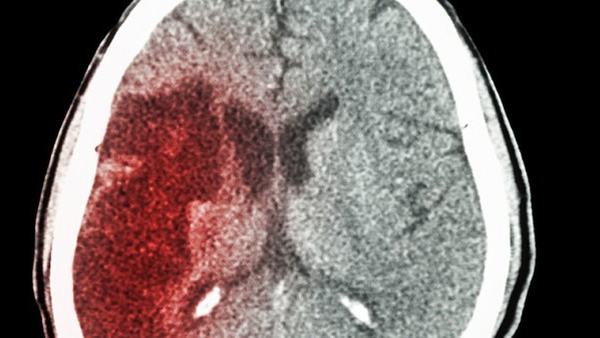

首先,患有小脑萎缩的人可能经历运动控制上的问题。小脑的主要功能之一是协调肌肉活动,因此患者可能会出现不协调的动作和不稳定的步态。他们可能会有困难走路、站立和保持平衡。日常活动,如写字、穿衣和吃饭,也可能变得困难。这些运动控制问题的严重程度会随着疾病的进展而加剧。

其次,小脑萎缩还可能导致神经系统症状的出现。患者可能出现颤抖(震颤),尤其在尝试做出精细动作时更为明显。他们的手可能会颤抖,使他们无法完成日常活动,如握笔或拧开瓶子盖子。此外,他们可能还会出现语言障碍,如言语不清或语速变慢。这些神经系统症状会严重影响患者的生活质量。

除了运动和神经方面的问题,小脑萎缩还可能引发认知和心理症状。患者可能会出现记忆力减退、思维变得迟缓和难以集中注意力的情况。他们可能会经历语言理解和表达的问题,并有丧失判断力的倾向。此外,情绪问题也很常见,包括焦虑、抑郁和易怒等。

最后,小脑萎缩还可能引发其他身体上的症状。患者可能出现头痛、眩晕和视力问题。他们的手部协调能力和精细度可能降低,使得日常生活中的简单任务变得困难。而且,小脑萎缩还会导致筋肉僵硬和痉挛的情况,给患者带来疼痛和不适。

总之,小脑萎缩是一种严重的神经系统疾病,会引发多种症状。这些包括运动控制问题、神经系统症状、认知和心理症状,以及其他身体上的症状。随着疾病的进展,这些症状可能变得更为严重,造成患者的生活困难和质量下降。虽然目前没有治愈小脑萎缩的方法,但早期诊断和综合治疗可以帮助患者减缓病情进展,并提供支持和改善生活质量的措施。